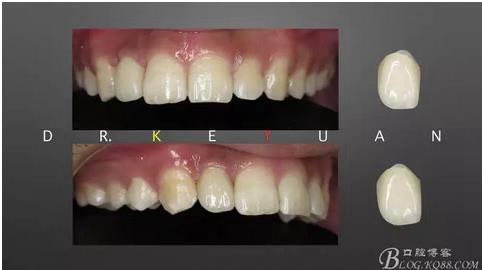

CASE 4—18歲少年,冠折后半年來診

360截圖20170120135125763.jpg

0、根管治療(千里之行始于根下)

360截圖20170120135136510.jpg

1、術(shù)前比色